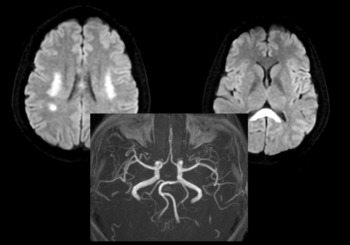

Đột quỵ không phải lúc nào cũng biểu hiện rõ ràng như méo miệng hay yếu liệt, nhiều trường hợp chỉ xuất hiện những dấu hiệu rất dễ bị bỏ qua khiến người bệnh mất “thời gian vàng” điều trị.

Chóng mặt là triệu chứng rất phổ biến, nhưng không phải lúc nào cũng vô hại. Trong nhiều trường hợp, đây có thể là dấu hiệu cảnh báo sớm của đột quỵ, đặc biệt khi kéo dài, dữ dội hoặc kèm theo các biểu hiện bất thường. Các bác sĩ khuyến cáo người dân cần nhận biết đúng để tránh nhầm lẫn nguy hiểm và không bỏ lỡ “thời gian vàng” điều trị.